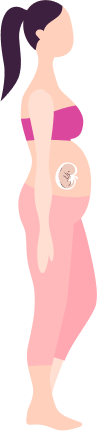

Taking Care of You and Your

Baby Pregnancy Timeline